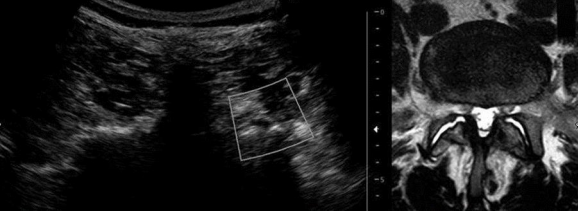

Figure 6

Transverse ultrasound image at the L4-L5 level showing facet arthrosis comparing with magnetic resonance image in the axial T2 plane.